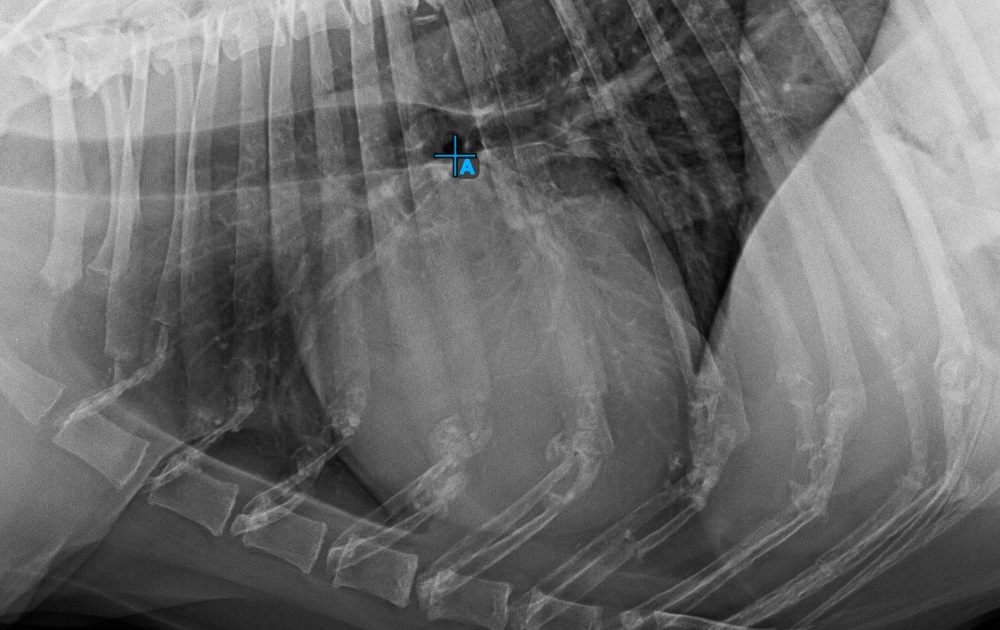

Start the measurement by marking the Bifurcatio tracheae, near the top of the heart.

Complete the long axis of the heart by marking the Apex point, near the bottom of the heart.